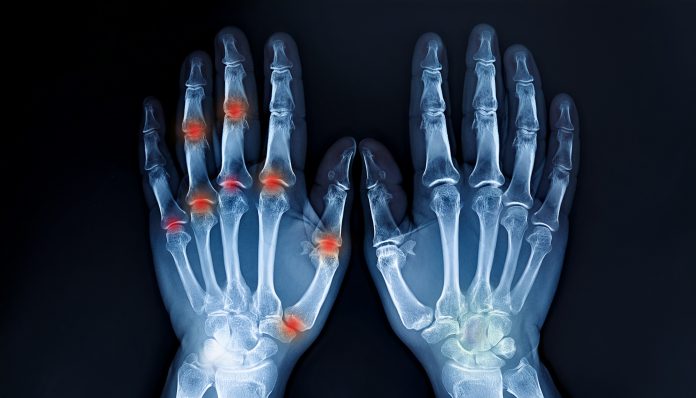

Mnoge osobe koje pate od reume, bolova u zglobovima ili trnjenja ruku često tragaju za nježnijim rješenjima. Jedan takav recept je pomogao ženi iz Cazina, koja je uspjela ublažiti svoje tegobe na prirodan način.

Ova žena iz Cazina godinama je trpjela bolove u zglobovima, trnjenje ruku i noćne grčeve koji su joj oduzimali san.

Već nakon nekoliko sedmica, žena je osjetila značajno poboljšanje. Bolovi su se smanjili, a trnjenje ruku potpuno nestalo. Kako kaže, nakon mjesec dana, ruke su joj bile kao nove, a svakodnevne aktivnosti postale su lakše. Bolovi su nestali, noćni grčevi su prestali, a osjećaj u prstima se vratio.

Deset godina nakon korištenja ovog prirodnog tretmana, ona tvrdi da nikada više nije osjetila stare bolove. Ovaj recept, zasnovan na prirodnim sastojcima, pokazao je svoju snagu. Med, lucerka i kišnica zajedno djeluju na poboljšanje cirkulacije, smanjenje upala i jačanje zglobova i kostiju.